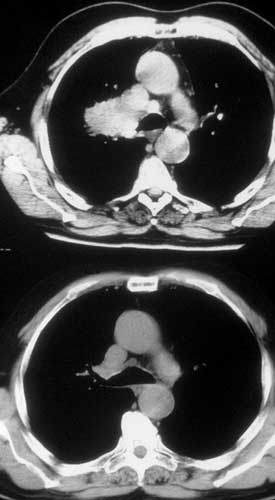

Infiltration of the PA on the right side requiring arterial reconstruction is less frequent. Partial resection of the PA often is performed in conjunction with right upper lobe sleeve resection (Figure 13). After right upper sleeve lobectomy en bloc with partial resection of the PA, the stump of the main bronchus and the PA defect are left open in the field (Figure 14). Harvesting of the pericardium is performed as above, based on the size of the portion of the resected pulmonary artery. Patch reconstruction of the PA is completed as above before reimplantation of the bronchus to reduce the arterial clamping time (Figure 15).

![]() |